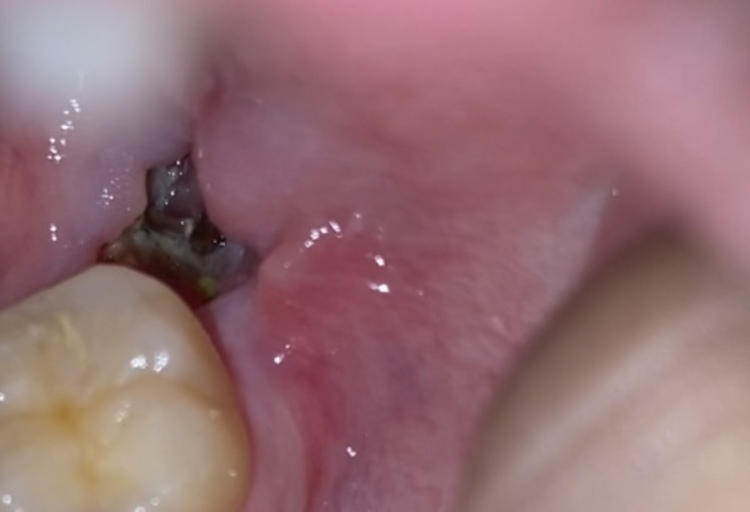

Tooth Extraction Healing: What's the White Stuff?

what is this white stuff ? is this a dry socket ??? im so paranoid after my wisdom teeth surgery : askadentist

Day 3 after wisdom tooth extraction. White stuff has formed on the blood clot, is this normal ? I just have the usual sore jaw and swollen cheek : wisdomteeth